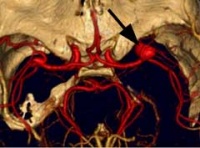

2.因颅内动脉瘤多位于颅底部WiLLis动脉环,直径小于1.0C的动脉瘤,CT不易查出。直径大于1.0cm,注射对比剂后,CT扫描可检出。MRI忧于CT,动脉瘤内可见流空。MRA可提示不同部位动脉瘤,常用于颅内动脉瘤筛选。三维CT(3D-CT)从不同角度了解动脉瘤与载瘤动脉的关系,为手术夹闭动脉瘤决策提供更多的资料。